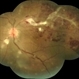

- Inflammatory Retinal Vein Occlusion

- Mallika Goyal, MD, Apollo Health City, Hyderabad

- Fundus camera

- Left eye sudden vision drop in a 21-year-old lady ANA positive with distal venous thrombosis with oral ulcers. Provisional rheumatological diagnosis is SLE. Treated with pulsed intravenous steroids with visual improvement.